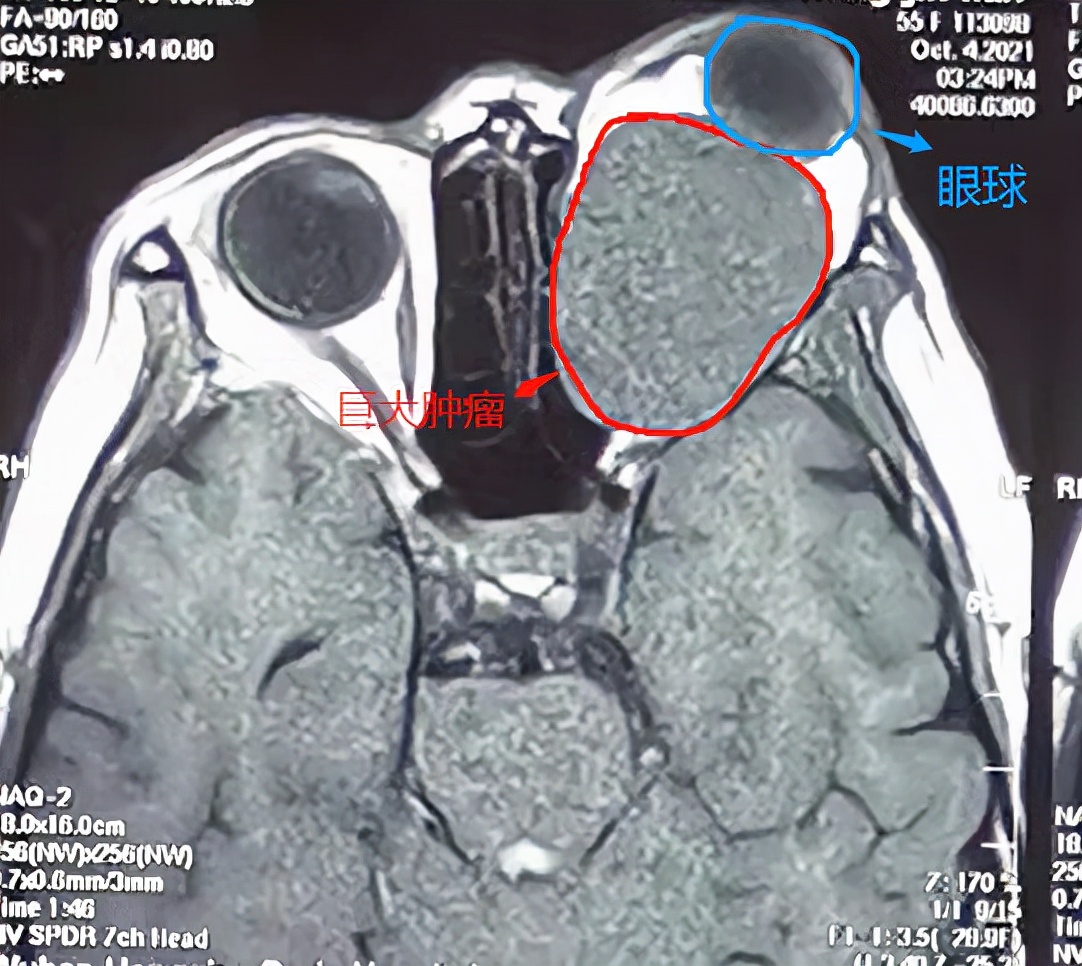

李女士影像检查图片

肿瘤长到“鸡蛋”大小,占据全部眼眶空间,挤压了眼眶造成了眼球脱臼 (眼球“跑出”眼眶外,这属于眼眶病的急诊),实属罕见。

且肿瘤严重压迫眼眶内神经血管,不仅大,位置还十分凶险,想要精准无误地切除肿瘤,还不伤及颅内、眼眶内重要的神经,无异于悬崖上走钢丝,还不带任何防护的那种。

程勉征主任团队仔细评估,为其定制定制个性化手术治疗方案,采用微创技术摘除肿瘤同时,帮助眼球复位,又不在眼部留明显疤痕,解除病痛又恢复容貌,手术进行了2个小时,肿瘤被完整切除(肿瘤长4.5cm*宽3.8cm)。